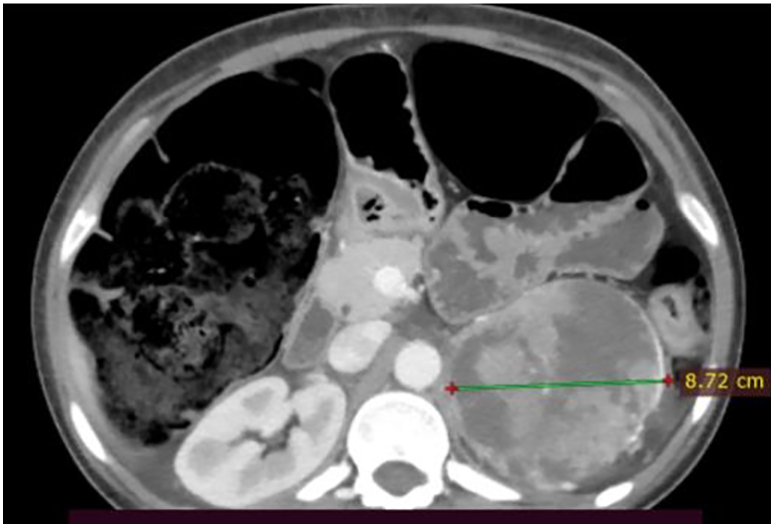

Serum metanephrine levels were significantly elevated, measuring 1203 pg/ml, complete blood count showed normochromic normocytic anemia, ESR was 140 mm/h, CRP 340 mg/L, HbA1C 6.72, serum potassium level 3.9 meq/L, and thyroid function tests were within normal limits. An ultrasound scan of the abdomen showed a left suprarenal mass. Abdominal CT showed a heterogeneous, hyper-vascular mass near the upper pole of the left kidney measuring 10.75 cm × 8.72 cm (Fig. 1).

Fig. 1.

Axial section of abdominal CT scan showing a big heterogeneous enhancing left adrenal mass and a hugely dilated colon.